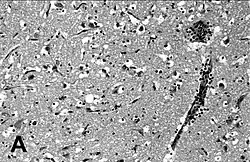

| Encephalitis in the cerebral cortex of a harbor seal with PDV, stained with hematoxylin and eosin | |